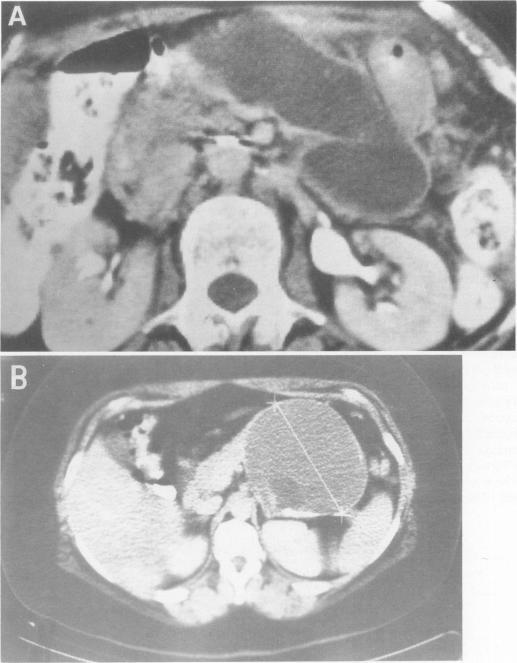

Within a 12-year period we treated 67 patients (49 women, 18 men; mean age, 61 years) with cystic neoplasms of the pancreas, including 18 serous cystic adenomas, 15 benign mucinous cystic neoplasms, 27 mucinous cystadenocarcinomas, 3 papillary cystic tumors, 2 cystic islet cell tumors, and 2 cases of mucinous ductal ectasia. Mean tumor size was 6 cm (2 to 16 cm). In 39% the patients had no symptoms, and in 37% the lesions had been misdiagnosed as a pseudocyst. Computed tomography was useful for detection, for distinguishing the microcystic subgroup of serous cystadenoma, and for showing rim calcification (all 7 cases were malignant) but was not reliable for distinguishing neoplasm from pseudocyst, serous from mucinous tumors, or benign from malignant. Arteriography showed hypervascularity in 4 of 10 serous adenomas, 3 of 11 mucinous carcinomas, and 1 of 1 papillary cystic tumors. Endoscopic pancreatography showed no communication with the cyst cavity in 37 of 37 cases of cystic neoplasms but opacified the ectatic ducts in 2 of 2 cases of mucinous ductal ectasia. Stenosis or obstruction of the pancreatic duct indicated cancer. The tumor was resected by distal pancreatectomy in 25 patients, by proximal resection in 29, and by total pancreatectomy in one, with no operative deaths. Forty-four per cent of the tumors were malignant. In 10 cases the tumor was unresectable because of local extension or distant metastases, and those patients died at a mean of 4 months. Seventy-five per cent of those resected for cure are alive without evident recurrence. Because the epithelial lining of the tumor was partially (5% to 98%) absent in 40% to 72% of cases of the major tumor types, and the mucinous component comprised only about 65% of mucinous cystadenoma lining, misdiagnoses on frozen and even permanent sections were made. Mitoses and histologic solid growth correlated with malignancy. Neuroendocrine elements were seen in 87% of benign and 47% of malignant mucinous tumors. It is recommended that the terms macrocystic and microcystic be abandoned in favor of the histologic designations serous and mucinous. Incomplete examination of the cyst wall can be misleading, however. It is suggested that mucinous ductal ectasia be recognized separately from cystic tumors and that all of these lesions be resected, with the possible exception of asymptomatic confirmed serous cystadenomas.

在12年期间,我们治疗了67例胰腺囊性肿瘤患者(49例女性,18例男性;平均年龄61岁),其中包括18例浆液性囊腺瘤、15例良性黏液性囊性肿瘤、27例黏液性囊腺癌、3例乳头状囊性肿瘤、2例囊性胰岛细胞瘤以及2例黏液性导管扩张症。肿瘤平均大小为6 cm(2至16 cm)。39%的患者无症状,37%的病变曾被误诊为假性囊肿。计算机断层扫描(CT)有助于检测、区分浆液性囊腺瘤的微囊性亚组以及显示边缘钙化(所有7例均为恶性),但在区分肿瘤与假性囊肿、浆液性肿瘤与黏液性肿瘤或良性与恶性方面并不可靠。动脉造影显示,10例浆液性腺瘤中有4例、11例黏液性癌中有3例以及1例乳头状囊性肿瘤中有1例表现为血管增多。内镜胰胆管造影显示(37例囊性肿瘤中的)37例囊肿腔与胰管不相通,但(2例黏液性导管扩张症中的)2例扩张导管显影。胰管狭窄或阻塞提示癌症。25例患者行胰体尾切除术,29例行胰头切除术,1例行全胰切除术,无手术死亡病例。44%的肿瘤为恶性。10例患者因局部侵犯或远处转移无法切除肿瘤,这些患者平均4个月后死亡。75%接受根治性切除的患者存活且无明显复发。由于在主要肿瘤类型的40%至72%病例中肿瘤上皮衬里部分(5%至98%)缺失,且黏液性成分仅占黏液性囊腺瘤衬里的约65%,因此在冷冻切片甚至永久切片上都出现了误诊。有丝分裂和组织学实性生长与恶性相关。在87%的良性和47%的恶性黏液性肿瘤中可见神经内分泌成分。建议摒弃“大囊性”和“微囊性”术语,而采用组织学名称“浆液性”和“黏液性”。然而,对囊肿壁检查不完整可能会产生误导。建议将黏液性导管扩张症与囊性肿瘤分开识别,并且除无症状的确诊浆液性囊腺瘤外,所有这些病变均应切除。